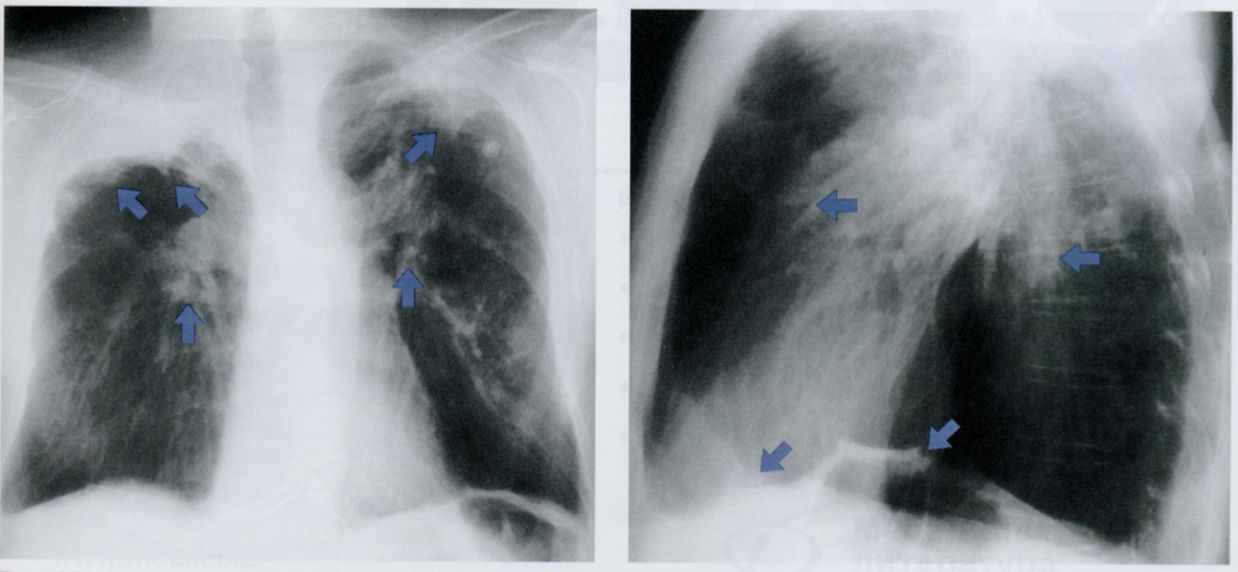

Верхушечные «шапки» за счет утолщенной плевры часто обнаруживаются в пожилом возрасте, но связывать их с туберкулезным процессом можно лишь при наличии внутрилегочного поражения. В этом случае верхушечные «шапки» более выражены.

На первом снимке показаны двусторонние плевральные «шапки» у пациента с туберкулезом. Натяжение фиброзной ткани на верхушках вызвало смещение обоих корней кверху (косые стрелки).

На рентгенограмме в БП четко видна полосовидная текстура плотного интерстиция (горизонтальные стрелки). Кроме того, на тень сердца проецируются очаги фиброза в переднебазальных участках плевры (косые стрелки, смотрят вниз).